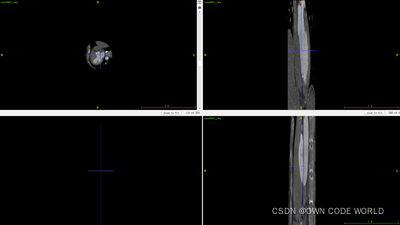

17.在这个模型中,测试出来的结果为下图.nii.gz格式的,因此我们可以使用ITK-SNAP软件来查看。

下面时使用ITK-SNAP软件来查看的结果图:

Img.nii.gz

pre.nii.gz

Img.nii.gz+ pre.nii.gz

Img.nii.gz+ gt.nii.gz

因为这组数据的dice有86%,所以效果还不错。